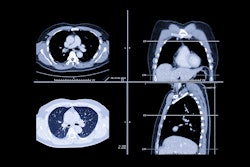

A team of researchers led by Jin Joon Park and Dr. Kyung Ah Kim, PhD, of the Catholic University of Korea in Seoul developed a 3D convolutional neural network (CNN) for diagnosing appendicitis on abdominopelvic CT scans. Their algorithm yielded at least 90% accuracy in testing both during internal validation and in external validation on CT scans acquired at other institutions on systems from a different vendor.

The research group sought to apply deep learning to see if it could help. They trained and validated a CNN using abdominopelvic CT exams from 667 patients who visited their hospital's ER with acute abdominal pain between December 2018 and May 2019. These included 215 cases with acute appendicitis and 452 with a normal appendix. All studies were acquired on a Discovery CT 750 HD scanner (GE Healthcare).